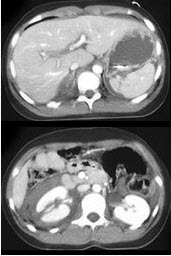

男,32岁,有外伤史,请根据所示图像,选择最可能诊断 ( )

• A、右肾挫伤

• B、右肾裂伤

• C、右侧肾上腺外伤性出血

• D、右肾挫伤合并右侧肾上腺外伤性出血

• E、右肾裂伤合并右侧肾上腺外伤性出血